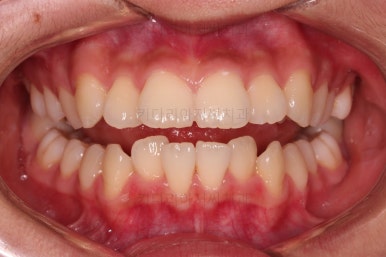

부산치아교정치과 키다리아저씨치과에서 마무리한 입안의 모습입니다.

가지런하게 잘 정렬이 되었고요.

윗니만 발치한 편악발치교정이지만 틈새 없이 공간이 닫혔으며 교합도 잘 맞습니다.

위아랫니가 가지런하게 보기 좋게 배열이 되었고요.

아랫니까지 윗니를 넣음으로써 튀어나와 보이던 앞니의 느낌이 좋아졌습니다.

물론 작은 아래턱에 맞춰 윗니를 뒤로 집어넣어야 해서 자칫 지나치게 들어간 입이 될까 염려되는 조심스러운 케이스였지만, 편악발치를 통해 최소한으로 입을 넣으면서 굉장히 조화롭게 잘 마무리 했습니다.

웃을 때 보이는 앞니의 느낌과 위치가 참 좋아졌네요.